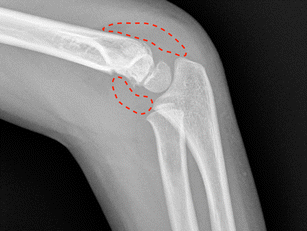

Supracondylar humeral fractures are the most common elbow fractures in children and represent 3 % of all paediatric fractures. The most common cause is a fall onto an outstretched hand with the elbow in extension, resulting in an extension-type fracture (97–99 % of cases). Currently, the Gartland classification is used, which has treatment implications. Diagnosis is based on plain radiographs, but accurate imaging could be limited due to patient pain. Based on fracture type, the definitive treatment could be either non-operative (type I) or operative (type III/IV); however, when handling type II fractures controversy remains. Neither pin configuration have shown higher efficacy over the other. Complications are ~1 %, the most common being pin migration, with compartment syndrome as the most devastating. Overall, functional outcomes are good, and physical therapy does not appear to be necessary.

Fig. 1

Fig. 2

Fig. 3

Fig. 4

Fig. 5

Fig. 6

Fig. 7